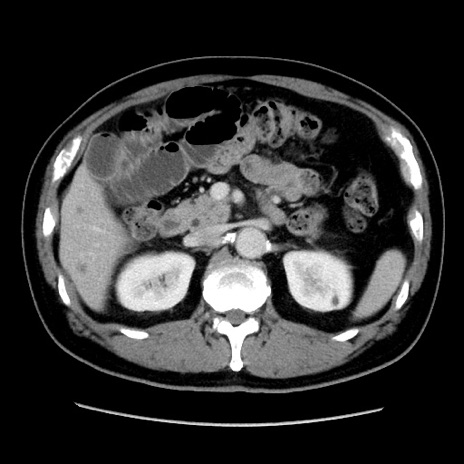

冠状断像

症例16(横断像)

【症例】 70歳代男性

【主訴】 腹痛、嘔吐

【現病歴】 約1ヶ月前より間欠的に腹痛と嘔吐あり、当院消化器内科を受診したところCTで多発する肝臓のLDAを指摘され、精査中であった。以降は消化器症状は安定していたが、2日前より嘔気と腹痛があり、同日より排便・排ガスが消失した。改善認めず、 本日、救急外来を受診した。

【既往歴】 大腸ポリープ切除後。

【身体所見】意識清明・会話良好、BT 36.3℃、BP 127/80mmHg、 P 80bpm、腹部:膨満あり、平坦・軟、上腹部正中および下腹部正中に圧痛あり、反跳痛なし、筋性防御なし。

【データ】WBC 7200、CRP 0.77